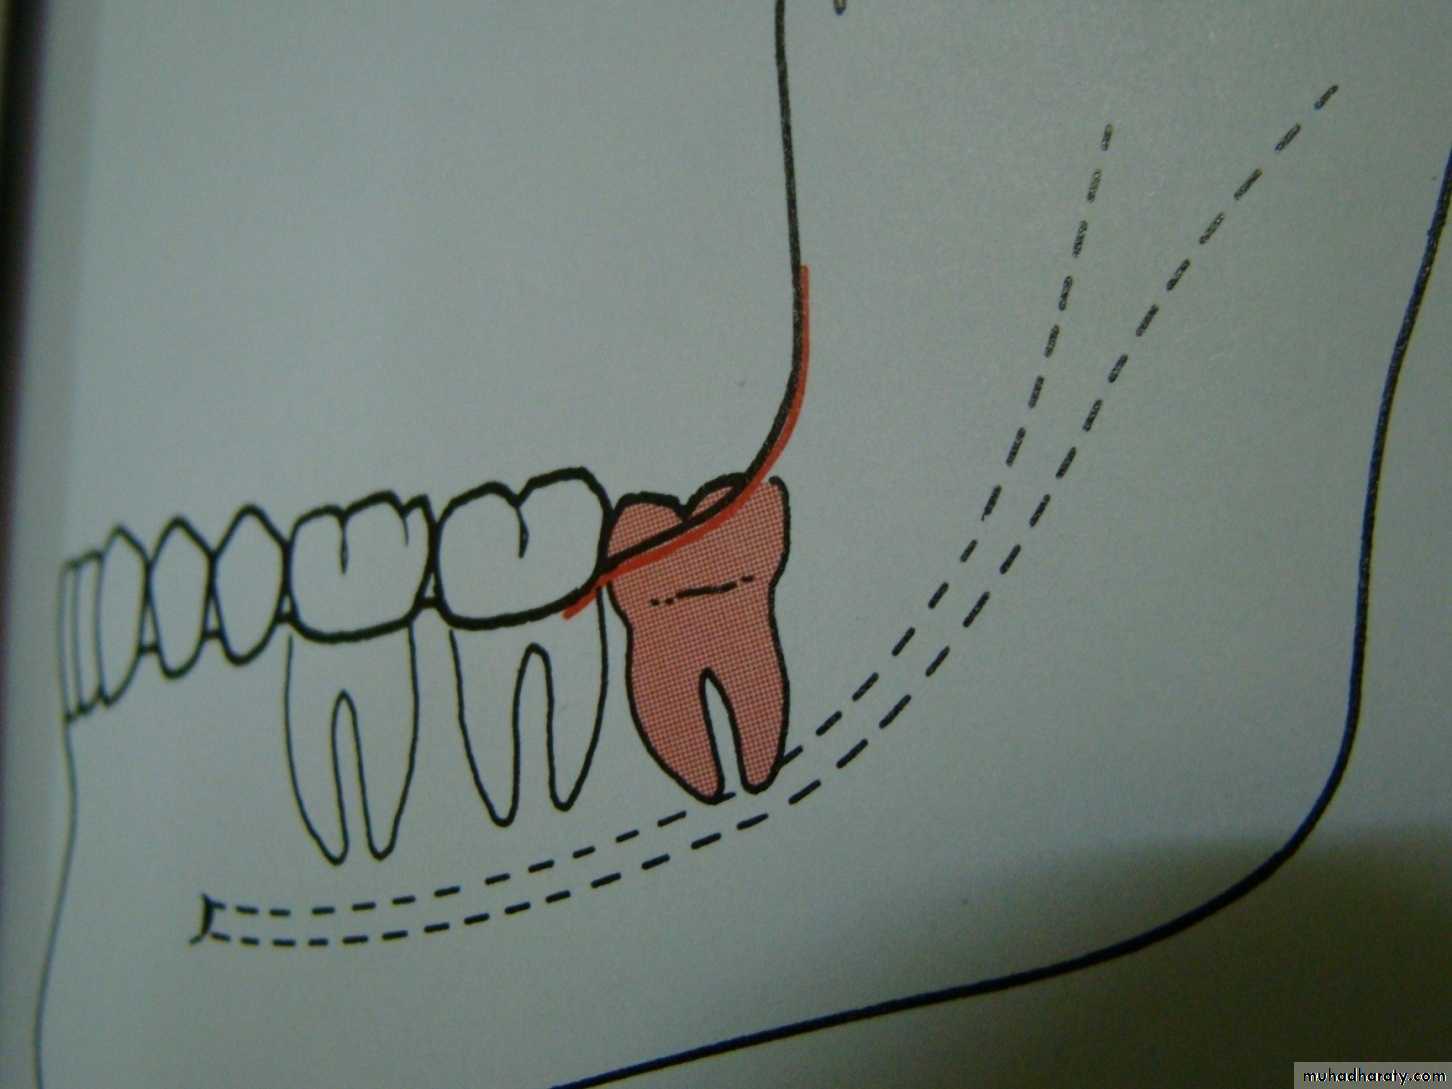

7 - Tooth in the fracture lineE.g Impacted lower third molar may weakens the angle of the mandible and make it more liable to fracture during trauma to the face .